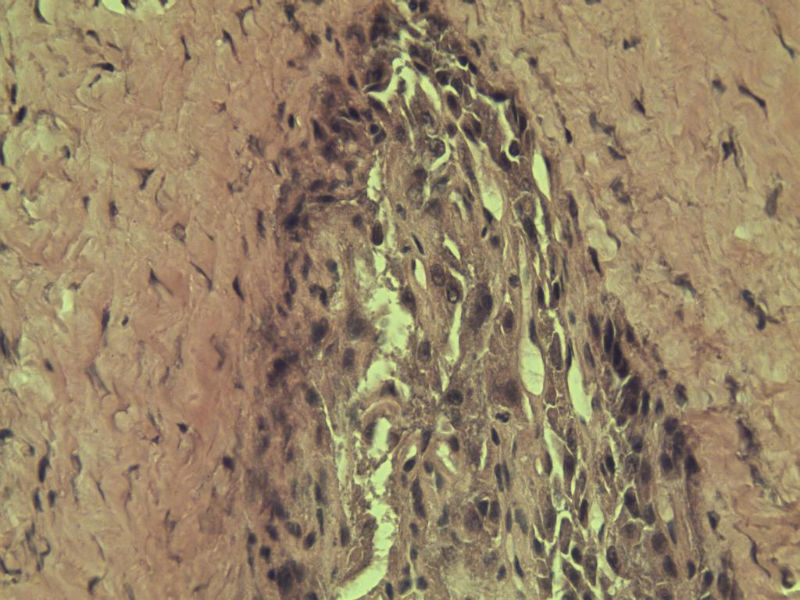

女 70岁 右颈部 头皮 多发皮下结节      取颈部部分结节送检 灰白小组织 1 块,直径 0.4 cm。 请问这个是什么?

肿瘤细胞大,上皮样,核空泡状,核仁明显,胞质嗜酸性或透明。

考虑:恶性黑色素瘤?

近心型上皮样肉瘤?

软组织透明细胞肉瘤?

上皮样多形性脂肪肉瘤?

等免疫组化标记!

此片染色欠佳,取材或切面也有问题,加大了诊断的难度,恶黑确实需要考虑,但其他一些转移癌也需要排除,比如肺癌之类的,还是期待免疫组化!